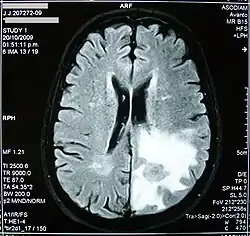

Edema cerebral é o acúmulo excessivo de líquido (edema) nos espaços intracelular e/ou extracelular do cérebro. Isso geralmente causa comprometimento da função nervosa, aumento da pressão dentro do crânio e pode levar à compressão direta do tecido cerebral e dos vasos sanguíneos. Os sintomas variam com base na localização e extensão do edema e geralmente incluem dores de cabeça, náuseas, vômitos, convulsões, sonolência, distúrbios visuais, tonturas e, em casos graves, coma e morte. Este incremento adiciona-se ao já provocado pela lesão primária, elevando a hipertensão intracraniana e propiciando as hérnias. O problema pode surgir tanto numa região delimitada como em todo cérebro. O diagnóstico e tratamento precoce são fundamentais para diminuir o risco de sequelas, melhorando o prognóstico. A abordagem de um edema cerebral quase sempre envolve a administração de diuréticos e corticosteroides.[1]